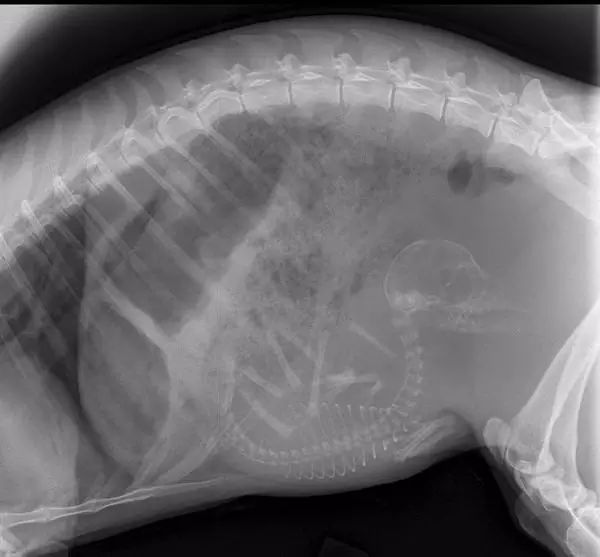

2. 乌龟。

应该可以做一个很酷的专辑封面。